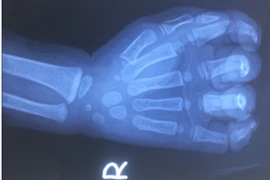

Người bệnh nhập viện trong tình trạng đa vết thương phần mềm bàn tay phải cho máy xay đa năng gây nên. Vết dao của máy xay đã cắt 7 vết thương khác nhau từ 1cmx1cm đến 3cmx1cm, gây đứt nhiều gân...